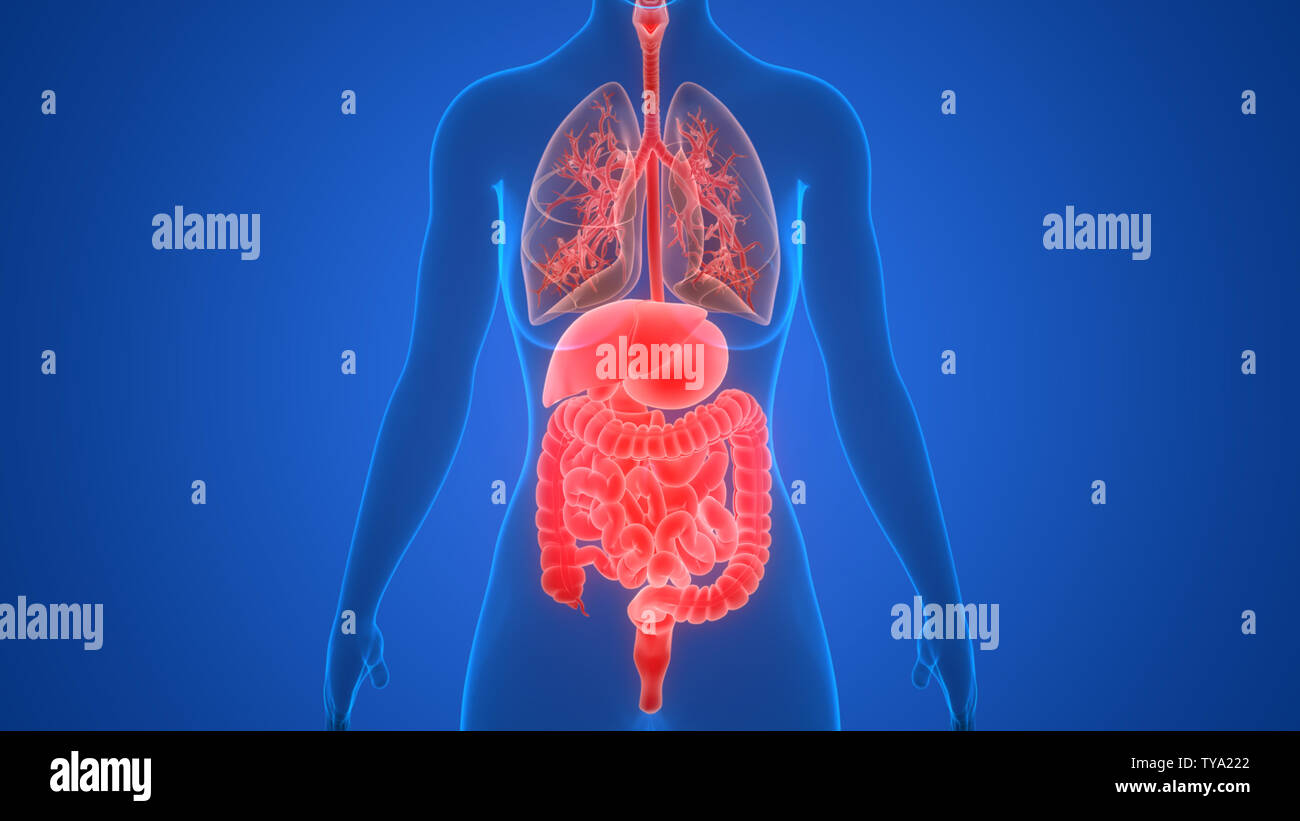

Human Internal Organs Anatomy Stock Photohttps://www.alamy.com/image-license-details/?v=1https://www.alamy.com/human-internal-organs-anatomy-image257762010.html

Human Internal Organs Anatomy Stock Photohttps://www.alamy.com/image-license-details/?v=1https://www.alamy.com/human-internal-organs-anatomy-image257762010.htmlRFTYA222–Human Internal Organs Anatomy